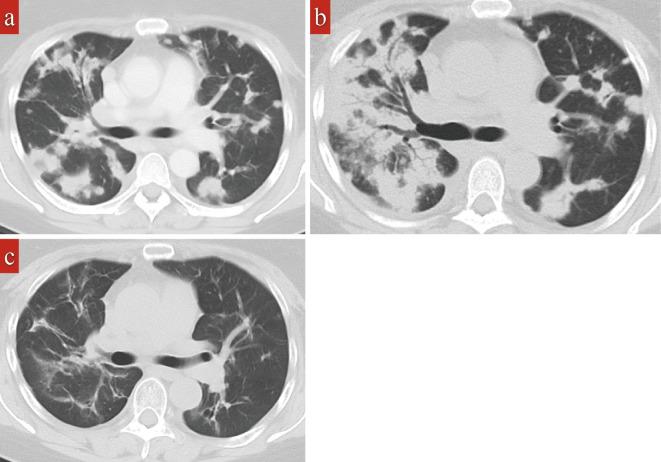

A 53-year-old woman had been diagnosed with rheumatoid arthritis (RA) in X-6. She was started on methotrexate (MTX) in X-1. She developed a cough, and chest computed tomography showed abnormalities. In X, MTX was discontinued, but the cough persisted. A lung biopsy revealed a diagnosis of nodular sclerosis classic Hodgkin lymphoma (CHL-NS). She was considered to have "other iatrogenic immunodeficiency-associated lymphoproliferative disorders" (OIIA-LPD), MTX-associated Hodgkin lymphoma (MTX-HL). She received six courses of brentuximab vedotin (BV) in addition to AVD (BV+AVD). A complete metabolic response was obtained, and the RA went into remission. This is the fourth reported case of BV+AVD for MTX-HL.

一位 53 岁女性于 X-6 年被诊断为类风湿关节炎(RA)。她于 X-1 年开始接受甲氨蝶呤(MTX)治疗。她出现咳嗽,胸部计算机断层扫描显示异常。在 X 年,停用了 MTX,但咳嗽仍持续存在。肺活检提示结节性硬化经典霍奇金淋巴瘤(CHL-NS)的诊断。她被认为患有“其他医源性免疫缺陷相关淋巴增生性疾病”(OIIA-LPD)、MTX 相关霍奇金淋巴瘤(MTX-HL)。她接受了六周期的 Brentuximab Vedotin(BV)联合 AVD(BV+AVD)治疗。获得完全代谢反应,RA 缓解。这是第四例报告的 MTX-HL 采用 BV+AVD 治疗的病例。